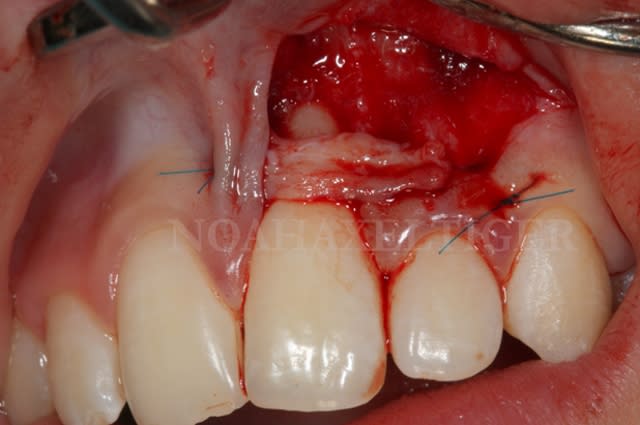

Mise en place du greffon conjonctif ejn6xx - Eugenol

Sutures e7ixmz - Eugenol